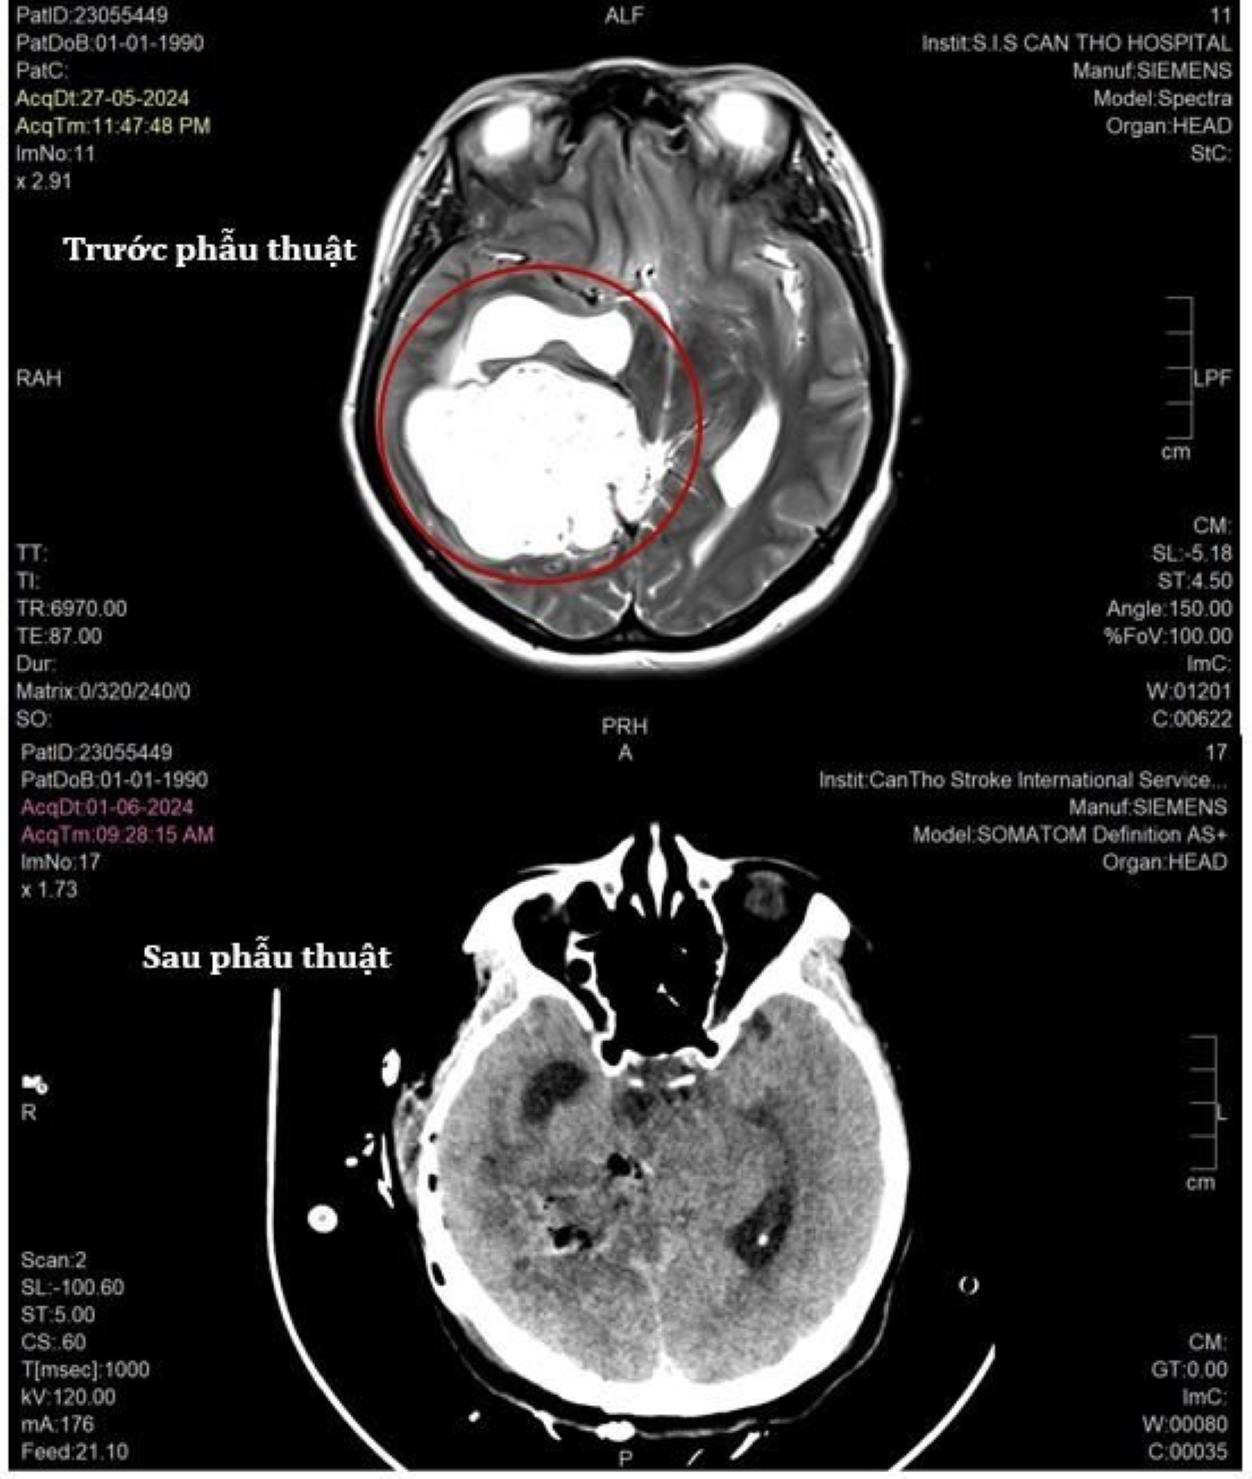

Qua thăm khám, các bác sĩ ghi nhận bệnh nhân có khối u màng não ở lều tiểu não vùng thái dương, chẩm phải, kích thước 55x60 mm.

Khối u này không chỉ nằm sâu ở trung tâm não mà còn dính vào các động mạch và dây thần kinh quan trọng, chèn ép các cấu trúc não cũng như phát triển lớn hơn sau 1 năm chưa được phẫu thuật với nhiều nguồn mạch máu nuôi.

Khối u lớn nằm sâu trong não của bệnh nhân. Ảnh: Bệnh viện cung cấp